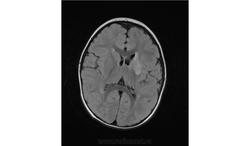

Помогите пожалуйста при постановке диагноза

Ребенок 2 года, заболели в середине декабре, гемипорез, к сожелению не могу ни как с контрасном исследованеим здесь загрузить но накапление контрасного вещества нет, спосибо за помочь!!!!!!!

Предположу гипоксически-ишемические изменения с диапедезным кровоизлиянием. Но они чаще двусторонние.